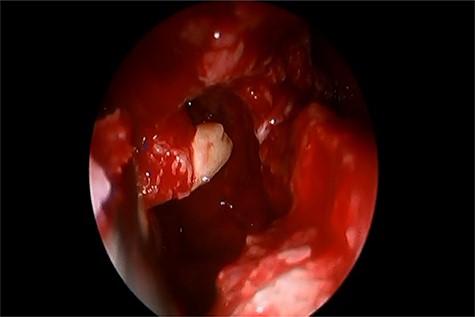

Informed consent was obtained from the parents and the patient underwent endoscopic endonasal enucleation of cyst and removal of ectopic tooth through inferior meatal antrostomy (Figs 2 and 3). Histopathologic examination confirmed the diagnosis of dentigerous cysts.

Inferior meatal antrostomy, after sac enucleation, while removing the tooth.